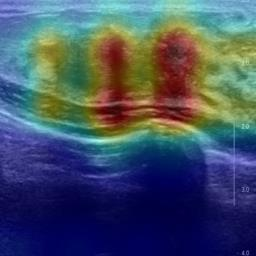

Ultrasonography is an important routine examination for breast cancer diagnosis, due to its non-invasive, radiation-free and low-cost properties. However, it is still not the first-line screening test for breast cancer due to its inherent limitations. It would be a tremendous success if we can precisely diagnose breast cancer by breast ultrasound images (BUS). Many learning-based computer-aided diagnostic methods have been proposed to achieve breast cancer diagnosis/lesion classification. However, most of them require a pre-define ROI and then classify the lesion inside the ROI. Conventional classification backbones, such as VGG16 and ResNet50, can achieve promising classification results with no ROI requirement. But these models lack interpretability, thus restricting their use in clinical practice. In this study, we propose a novel ROI-free model for breast cancer diagnosis in ultrasound images with interpretable feature representations. We leverage the anatomical prior knowledge that malignant and benign tumors have different spatial relationships between different tissue layers, and propose a HoVer-Transformer to formulate this prior knowledge. The proposed HoVer-Trans block extracts the inter- and intra-layer spatial information horizontally and vertically. We conduct and release an open dataset GDPH&GYFYY for breast cancer diagnosis in BUS. The proposed model is evaluated in three datasets by comparing with four CNN-based models and two vision transformer models via a five-fold cross validation. It achieves state-of-the-art classification performance with the best model interpretability.

翻译:超声波分析是乳腺癌诊断的一个重要常规检查,原因是其非侵入性、无辐射和低成本的特性。然而,由于其内在局限性,它仍不是乳腺癌的第一线筛选测试。如果我们能够精确地通过乳房超声图像诊断乳腺癌(BUS),它将是一个巨大的成功。我们提出了许多基于学习的计算机辅助诊断方法,以实现乳腺癌诊断/感官分类。然而,其中多数方法需要事先确定性能模型,然后对ROI内部的跨值进行分类。常规分类支柱,如VGG16和ResNet50等,可以在没有ROI要求的情况下实现有希望的分类结果。但是这些模型缺乏可解释性,从而限制了其在临床实践中的使用。在本研究中,我们提出了一个新的无乳腺癌诊断模型,在超声波图像中进行解释性特征描述。我们利用了先前的解剖学学学知识,即恶性肿瘤和良性肿瘤模型在不同组织层之间有着不同的空间关系,并提议采用状态解析法来编制这一先前的知识。拟议中的HOVer-Trans-Trading-Tradef-trainal Ex-deal-dealal-deal-deal-deal-degraphal-deal-deal-deal-deal-deal-deal disal disal-dal-dal-dal-dal-dal-deal-deal-dal-deal-deal-deal-dal-dal-dal-dal-dal-dal-dal-dal-dal-dal-dal-dal-dal-dal-I-dal-Iversal-dal-Ial-d-d-I-d-d-I-I-I-I-I-I-I-I-I-I-I-I-I-I-I-I-I-I-I-I-I-I-I-I-I-Ial-I-Ial-Ial-I-I-I-I-I-I-I-I-I-I-I-I-I-I-I-I-I-I-I-I-I-I-I-I-I-I-I-I-I-I-I-I-